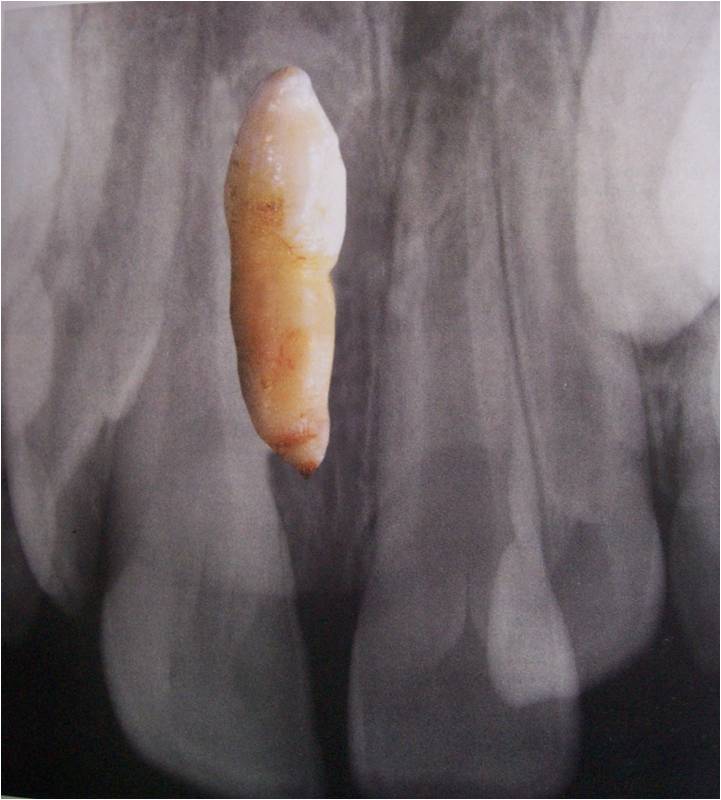

Radiographic diagnosis

When should we suspect canine impaction?

Critical period – 8 to 11 years

Radiographic examination mandatory if there is no eruption after the critical age.

11 years appears to be the critical age.